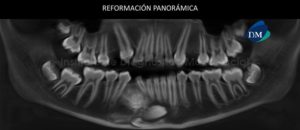

Paciente femenino, 20 años de edad acude al Instituto de Diagnóstico Maxilofacial (IDM) para su evaluación previo a tratamiento de ortodoncia. A la evaluación de